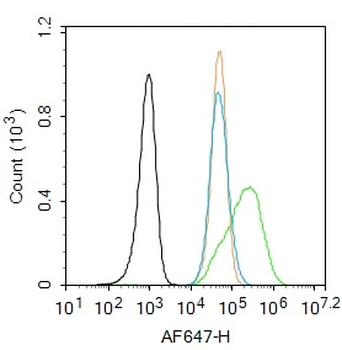

Phospho-Smad3 (Ser423 + Ser425) Rabbit Polyclonal Antibody [orb6983]

FC, IF, IHC-Fr, IHC-P, WB

Bovine, Canine, Equine, Gallus

Human, Mouse, Porcine, Rat

Rabbit

Polyclonal

Unconjugated

100 μl, 200 μl, 50 μlPhospho-SMAD5 (Ser463 + Ser465) Recombinant Rabbit Monoclonal Antibody [orb559123]

50 μl, 100 μlPhospho-Smad3 (Thr179) Rabbit Polyclonal Antibody [orb313112]

FC, ICC, IF, IHC-Fr, IHC-P

Bovine, Canine, Equine, Porcine, Sheep

Human, Mouse, Rat

Rabbit

Polyclonal

Unconjugated